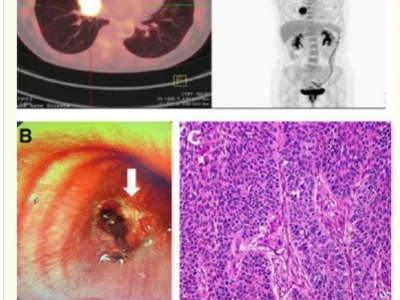

Opis przypadków leczenia wodorem molekularnym

Opublikowany : 2020-12-15 - Par Eugeniusz | Kategorie : Wodór molekularny konta nowotworyLekarze opisują autentyczne przypadki wyleczenia wodorem molekularnym

Opublikowany : 2020-12-15 - Par Eugeniusz | Kategorie : Wodór molekularny konta nowotworyLekarze opisują przypadki leczenia wodorem molekularnym

Opublikowany : 2020-12-15 - Par Eugeniusz | Kategorie : Wodór molekularny konta nowotworyPrzypadki opisane przez lekarzy ze szpitali